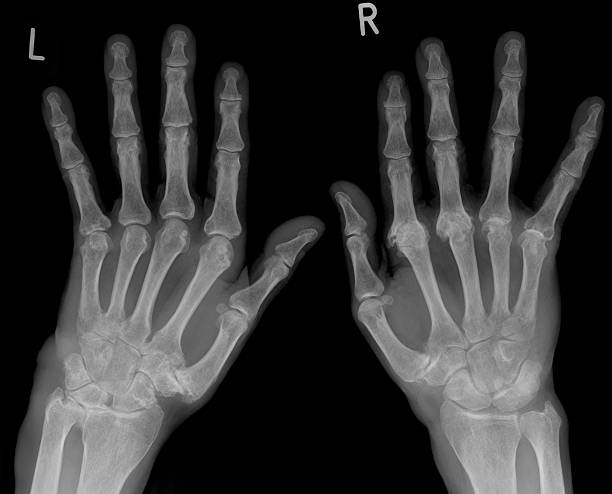

류마티스 관절염(Rheumatoid Arthritis, RA)은 자가면역 질환의 일종으로, 면역 체계가 자신의 관절을 공격하여 염증을 유발하는 만성 질환이에요. 시간이 지나면서 관절이 손상되고 변형될 수 있으며, 전신 피로와 통증을 동반하는 경우가 많아요.

| 대칭적인 관절염 | 양쪽 손, 발, 무릎 등 대칭적으로 관절염 발생 |

류마티스 관절염의 증상은 관절의 염증과 통증이 가장 대표적이지만, 전신적인 증상도 함께 나타날 수 있어요. 초기에는 미미한 불편함으로 시작되지만, 조기에 치료하지 않으면 관절 변형과 기능 저하로 이어질 수 있어요.

| 손가락 및 발가락 변형 | 심해지면 관절이 휘어지거나 변형될 수 있음 |